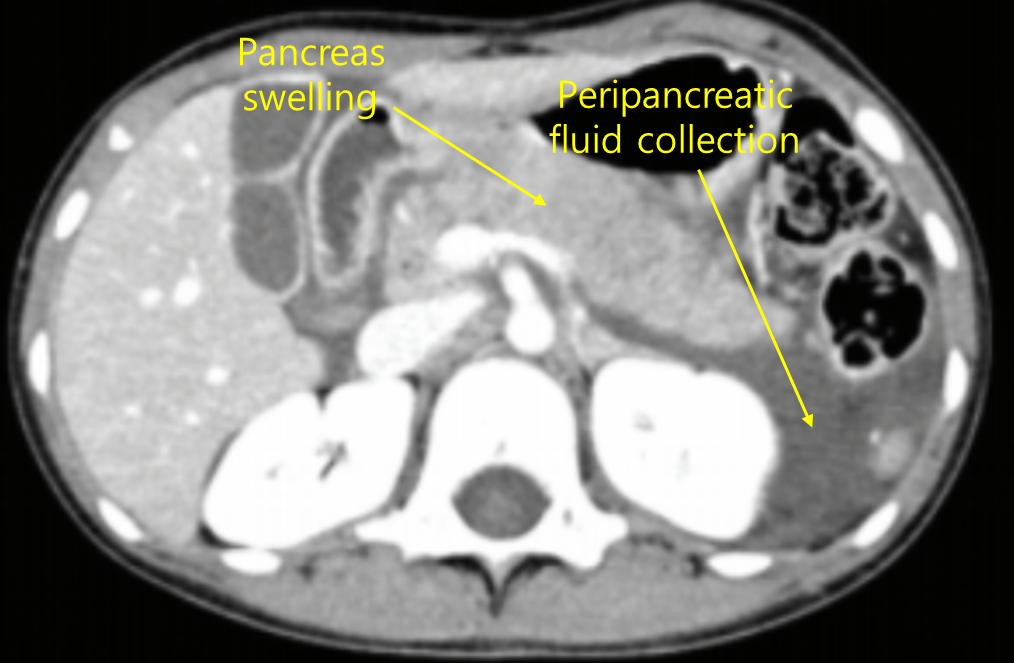

건강하던 5세 남아가 복통으로 병원에 왔다. 5일 전부터 구토와 왼쪽 등쪽으로 뻗치는 윗배 통증이 있었다. 식사 후에 통증과 구토가 더 심해져 잘 먹지 못하였다. 2일 전부터 쌀미음만 먹으면서 통증과 구토는 많이 호전된 상태이다. 배꼽 위 5 cm 부근에 가벼운 압통이 있으나 반동압통은 없다. 혈액검사 결과는 다음과 같다. 배 컴퓨터단층촬영 사진이다. 처치는?

백혈구 9,500/mm3 (중성구 53%, 림프구 38%), Na+/K+/Cl- 138/4.2/99 meq/L, 칼슘/인 9.2/4.8 mg/dL, 총단백질/알부민 7.6/4.0 g/dL, 아밀라아제 220 U/L (참고치, 20~96), 리파제 260 U/L (참고치, 3~43), C-반응단백질 9 mg/L (참고치, <10)

Img | CT: Edematous pancreas, peripancreatic fluid collection |

• 혈액 검사상 lipase, amylase가 상승해 있으며, CT상 급성 췌장염 소견이 관찰된다. 진단 기준 3가지 (복통, 혈액검사, 영상 소견) 모두를 만족하므로 급성 췌장염으로 진단 가능하다.

진단 | • US: 담석, 담관확장 확인 • CT: 췌장 실질의 edema, 췌장 근처 조직의 inflammation |